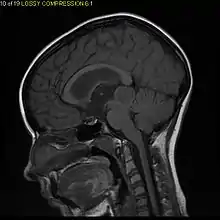

Pilocytic astrocytomas are often cystic, and, if solid, tend to be well-circumscribed. They are characteristically easily seen on computed tomography (CT scans) and magnetic resonance imaging (MRI).

Usually – depending on the interview of the patient and after a clinical exam which includes a neurological exam and an ophthalmological exam – a CT scan and/or an MRI scan will be performed. A special dye may be injected into a vein before these scans to provide contrast and make tumors easier to identify. The neoplasm will be clearly visible.

Visual aspect

Microscopically, an astrocytoma is a mass that looks well-circumscribed and has a large cyst. The neoplasm may also be solid.